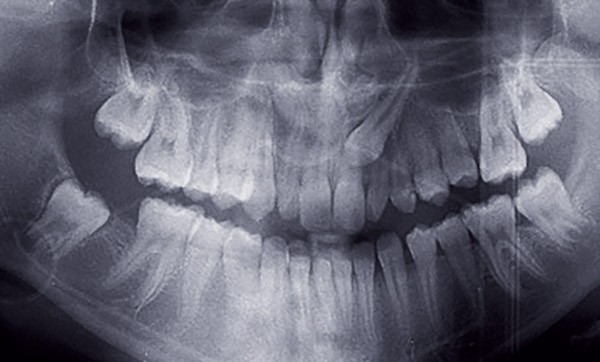

Les canines maxillaires incluses sont régulièrement rencontrées en pratique quotidienne : environ 1,7 % de la population générale est affectée [1]. Ce sont les dents les plus fréquemment incluses après les 3e molaires [2]. Les inclusions palatines sont deux fois plus fréquentes que les vestibulaires [3]. Les complications les plus fréquentes sont les résorptions externes des racines des incisives adjacentes, retrouvées dans 50 % des cas [4]. Dotées d’une longue racine, solidement ancrées dans l’os alvéolaire et positionnées aux angles de l’arcade maxillaire, elles sont considérées comme des dents stratégiques [5]. L’objectif de leur prise en charge est de les positionner correctement sur l’arcade, en reconstituant un parodonte sain, une occlusion fonctionnelle, et en améliorant l’esthétique [6].

Le traitement des canines incluses constitue un véritable défi clinique. Il requiert une approche pluridisciplinaire impliquant une étroite collaboration entre le chirurgien-dentiste traitant, l’orthodontiste et le chirurgien oral. Pour aider les praticiens à relever ce défi, des recommandations internationales de bonne pratique ont été émises en Angleterre [7], aux États-Unis [8] et en France [6]. Elles ont pour objectif de clarifier le diagnostic et la prise en charge des différents intervenants et de favoriser une décision thérapeutique pluridisciplinaire, précoce et adaptée.

Démarche diagnostique

Le diagnostic positif d’une canine incluse résulte de la confrontation des données cliniques et radiologiques. Les facteurs qui doivent faire suspecter l’inclusion d’une canine maxillaire sont au nombre de 4 : la persistance de la canine temporaire au-delà de la date normale…